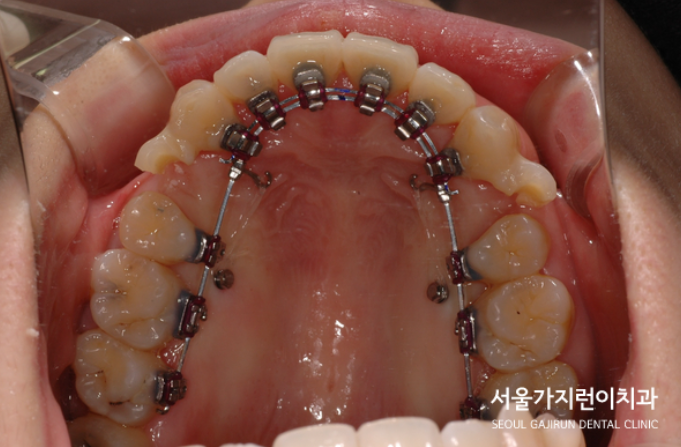

환자분의 경우 투명교정으로도 돌출입 교정이 가능했지만 상대적으로 치료기간이 길어질 것이 예상되어 설측교정을 선택하셨는데요. 서울가지런이치과 교정과 의원의 특화된 탄댐 아치 와이어 테크닉 방법을 이용해 상악 전치의 치근과 치관을 같은 비율로 후방이동시킬 수 있었습니다. 치료과정에서 돌출감 해소를 위해 상하악 제1소구치를 발치 했는데요. 발치간 공간을 폐쇄하기 위해 미니스크류도 식립하여 진행했습니다.

발치 공간이 메꿔지면서 입술이 들어가는 것을 확인할 수 있었는데요. 환자분의 경우 턱끝에 호두껍질 모양의 주름이 생기지 않길 희망하셨기 때문에 미니스크류를 식립한 후에 교정용 고무줄을 연결해 안정적으로 힘이 가해지도록 진행했습니다. 총 소요된 치아교정기간은 약 1년 6개월 정도인데요. 교정 치료 후 사진을 보면 옥니 느낌 없이 윗 입술이 들어간 것도 확인할 수 있었습니다.